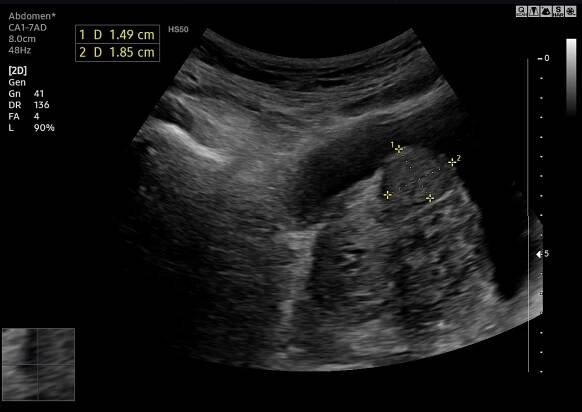

Sono-Atlas - GP Medical Center Westend